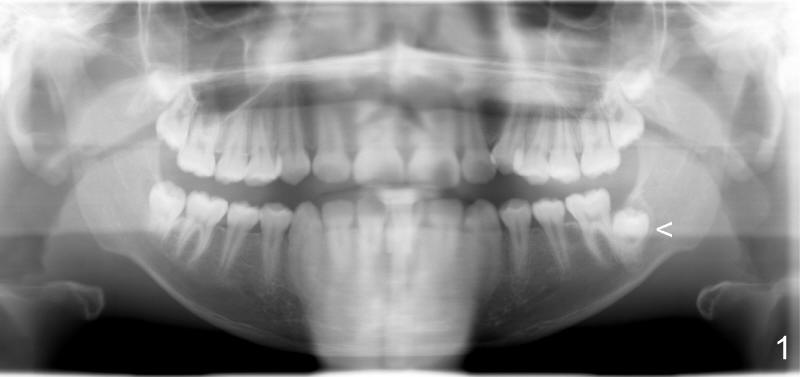

Impacted Lower 2nd Molar

Xin Wei, DDS, PhD, MS 1st edition 09/07/2011, last revision 09/07/2011